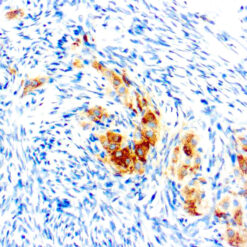

Iba1 (AIF1)

Actin-binding protein that enhances membrane ruffling and RAC activation. Enhances the actin-bundling activity of LCP1. Binds calcium. Plays a role in RAC signaling and in phagocytosis. AIF1 colocalizes with actin, and upon stimulation, translocates to lamellipodia. It is also a marker of human microglia and is expressed by macrophages in injured skeletal muscle. The gene encoding AIF1 resides in the tumor necrosis factor (TNF) cluster of genes, located in the region represented by the human major histocompatibility complex (MHC).

| Cellular Localization | Cytoplasmic and Cell Surface |